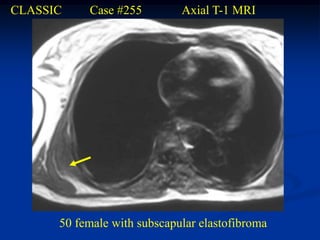

Elastofibroma

The elastofibroma is seen almost exclusively in people past the

age of 55 years. It is more common in women than men, and the

majority of cases are seen in those involved in heavy manual labor

or unusual sports requiring extensive use of the upper extremities.

It almost always occurs between the scapula and the chest wall

inferiorly and is bilateral in about 10% of cases. It is usually located

in the lower subscapular area, deep to the rhomboid and latissimus

dorsi muscles where it is firmly attached to the chest wall in the area

of the seventh and eighth ribs posteriorly. Grossly, the tumor has an

appearance similar to a desmoid tumor and microscopically there is

an intertwining of swollen eosinophillic collagen fibers and elastic

fibers in an equal proportion. The elastic fibers have a degenerated,

beaded appearance or are fragmented into small globules or droplets

that are easily seen with the Verhoeff stain that is specific for elastin

fiber. The cross section shows a characteristic serrated edge. The

elastofibroma is considered a reactive pseudotumor with an excellent

prognosis. It is treated by a marginal surgical resection with an

extremely low recurrence rate and in some cases can be treated by

radiation therapy alone without surgery.

CLASSIC    Case #255         Axial T-1 MRI

50 female with subscapular elastofibroma